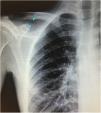

Varón de 24 años, con antecedentes de enfermedad de Crohn ingresa por dolor en fosa ilíaca derecha (FID) objetivándose en la TAC abdominal perforación ileal, se le realiza una hemicolectomía derecha y resección ileal urgente. El séptimo día postintervención, tras la retirada del catéter venoso central (CVC) subclavia derecha, presenta episodio brusco de disnea y dolor subcostal derecho, desaturación, sudoración profusa con recuperación tras oxigenoterapia. A las pocas horas, mientras deambula, presenta mareo, disnea súbita con desaturación hasta el 50% y taquipnea. Índice de Glasgow: 6 puntos (AO: 4, RM: 1 y RV: 1), rigidez de extremidades y desviación conjugada de la mirada a la derecha. Se descartó enfermedad isquémica/hemorrágica cerebral. Se realiza angio-TAC pulmonar apreciándose enfisema subcutáneo a nivel infraclavicular derecho (flecha lila), con aire a nivel de la vena subclavia derecha compatible con embolia gaseosa (flecha blanca), sin apreciarse aire en cavidades cardíacas, ni en arterias pulmonares principales (fig. 1). En la Rx de tórax se aprecia zona radiolúcida a nivel infraclavicular derecho (flecha azul) en la localización de CVC subclavia derecha (fig. 2). El paciente presenta buena evolución con recuperación del nivel de conciencia manteniéndose oxigenoterapia con VMK reservorio y posición en Trendelenburg, y tras 48h de ingreso en la UCI pudo darse de alta a la planta.